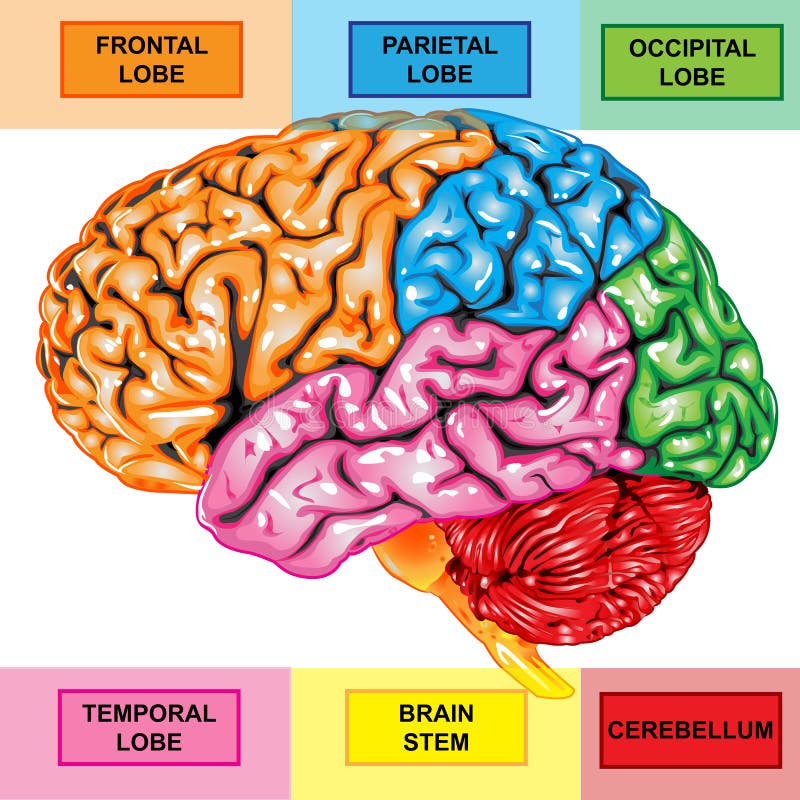

έννοια της τεχνητής νοημοσύνης. άνθρωπος-εγκέφαλος με σύμβολο τεχνητής νοημοσύνης.